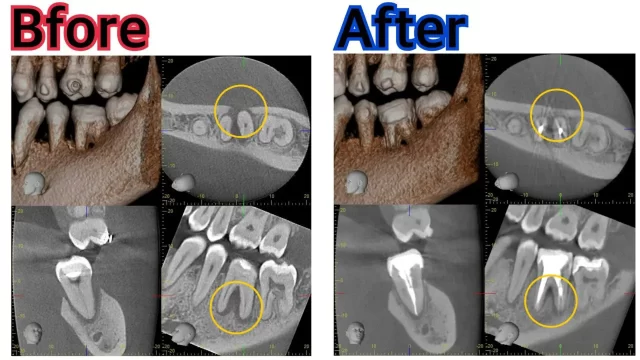

こちらは部分的なレントゲンとCTです。

かなり大きい病変があり、歯を支えている骨が溶けています。

治療前後のデータをご覧下さい。

病変も縮小し、溶けていた骨も回復しました!